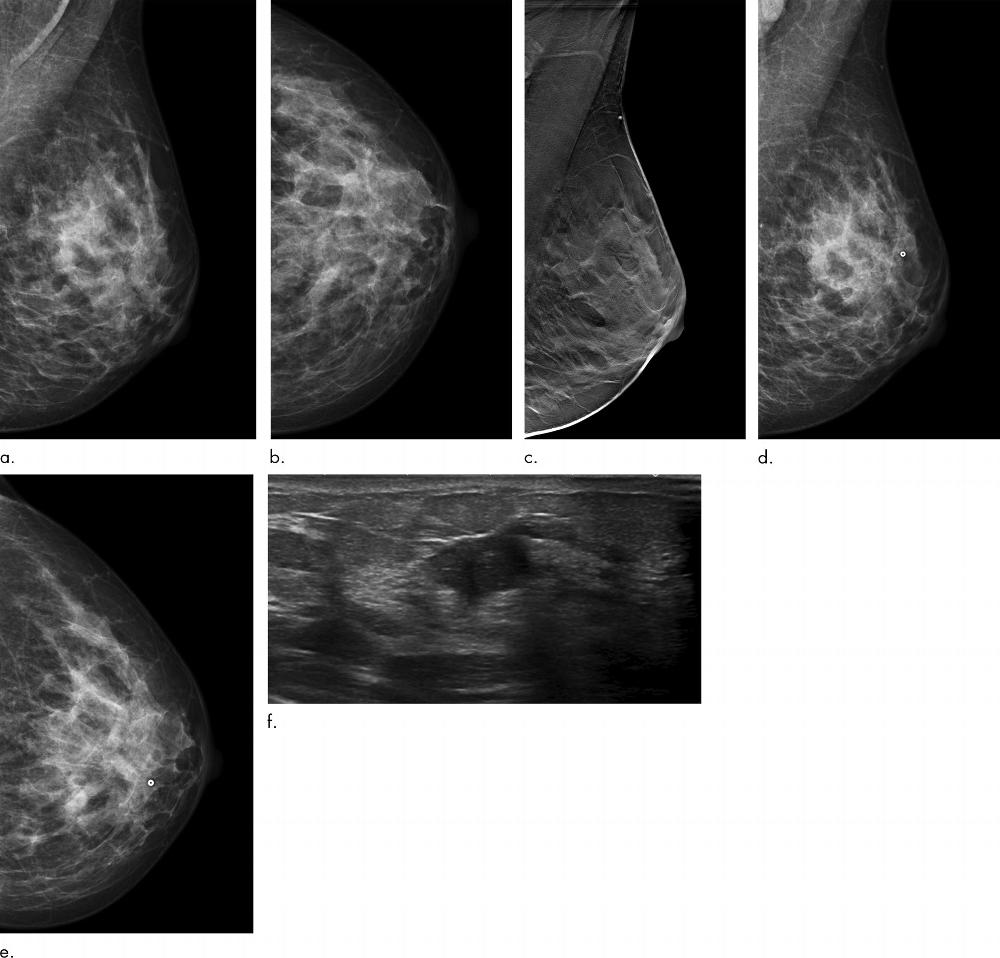

Figure 3. Images in a 43-year-old woman diagnosed with a 13-mm lymph node–positive invasive ductal carcinoma luminal B–like human epidermal growth factor receptor 2 breast cancer 7 months after a screening negative for cancer in the Malmö Breast Tomosynthesis Screening Trial. (a) Mediolateral and (b) craniocaudal digital mammography (DM) images at screening. (c) Digital breast tomosynthesis screening image. (d) Mediolateral and (e) craniocaudal DM images at diagnosis with a small marker at lump location. The breast cancer is difficult to distinguish. (f) US image at diagnosis; breast cancer clearly visible.